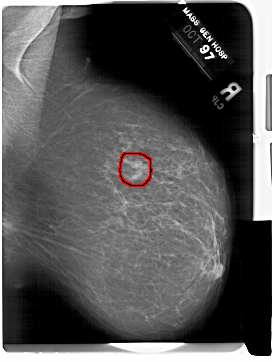

A_1583_1.RIGHT_MLO

RIGHT_MLO LINES 6871 PIXELS_PER_LINE 5161 BITS_PER_PIXEL 12 RESOLUTION 43.5 OVERLAY

FILE: A_1583_1.RIGHT_MLO.OVERLAY

TOTAL_ABNORMALITIES 1

ABNORMALITY 1

LESION_TYPE MASS SHAPE IRREGULAR MARGINS ILL_DEFINED

ASSESSMENT 4

SUBTLETY 4

PATHOLOGY MALIGNANT

TOTAL_OUTLINES 1

BOUNDARY